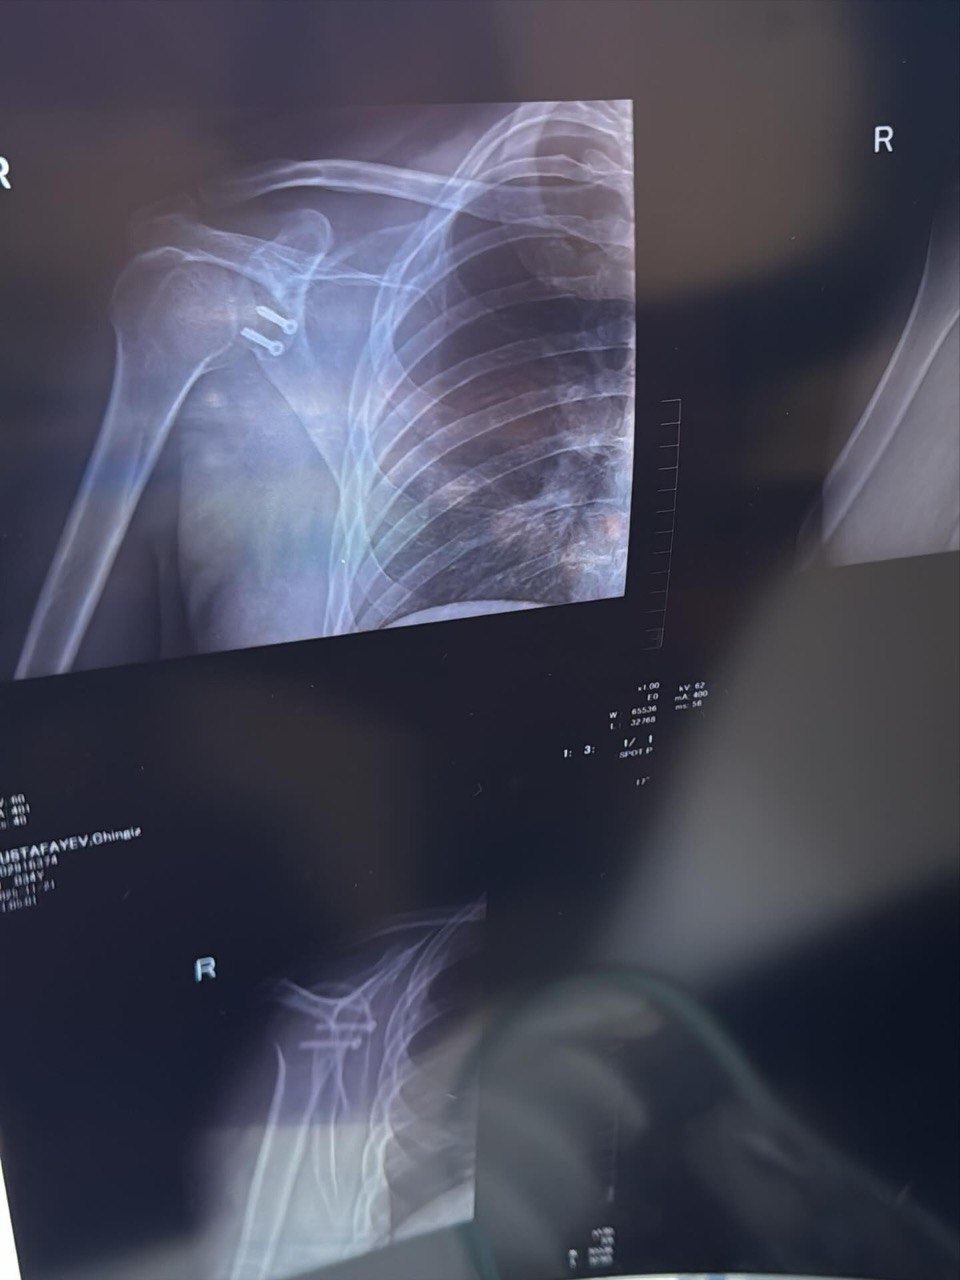

“5 il ərzində çiynim 7 dəfə çıxıb. Hər dəfə eyni ağrı, eyni qorxu, eyni narahatlıq… İdman da, aktiv həyat da tam mümkün olmurdu. Hər dəfə özümə deyirdim: “hələ tezdir, bir az da gözləyim bir söznən iş güc və sairə…” Amma 2 ay əvvəl sonuncu dəfə çiynim çıxanda anladım ki, artıq bu məsələni həll etməyin vaxtı gəlib.

Qərar verdim və sağlığımı ürəyimə yatan, ilk görüşdən etibarımı qazanan həkimə həvalə etdim və nəhayət dünən əməliyyat olundum. İndi uzun bir reabilitasiya dövrü başlayır.

Eyni problemi yaşayan dostlara isə bir sözüm var: Gözləməyin. Mənim kimi illərlə səbr etməyin. Hər çıxıq çiyni daha çox zədələyir. Vaxtında əməliyyat — gələcək həyatınızı xilas edir”.